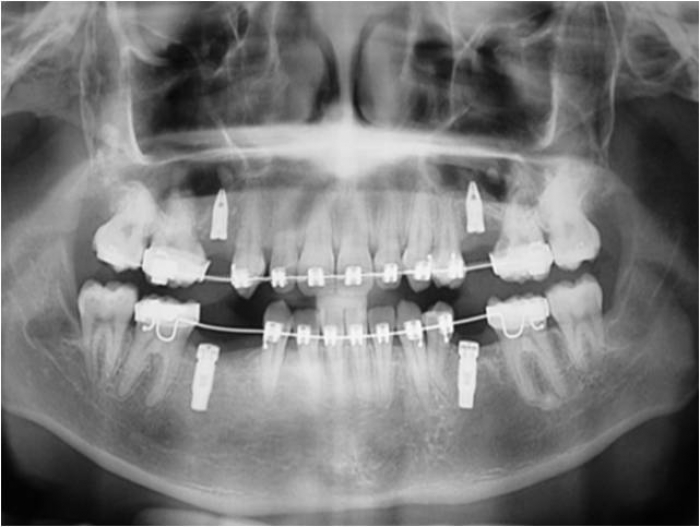

Raio x inicial, com agenesia de dentes permanentes